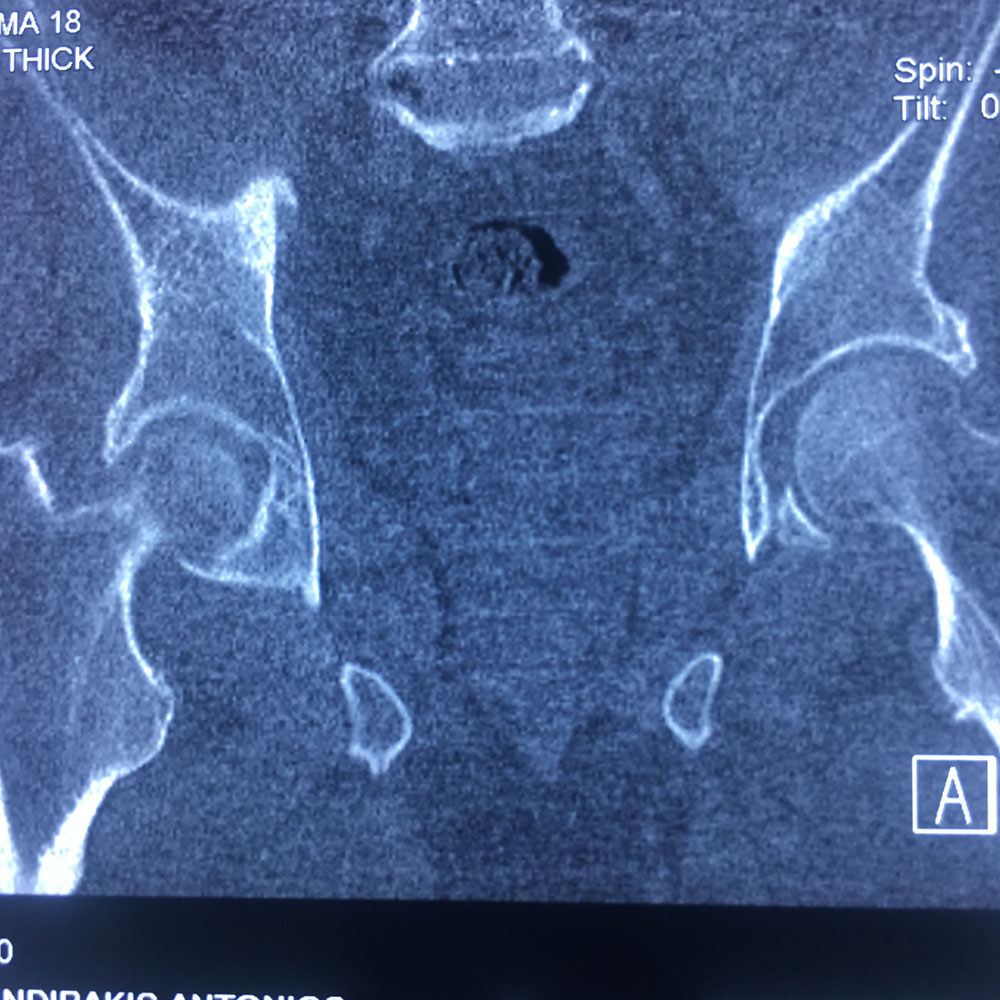

Εικόνα 1(α,β,γ,δ): Οι ακτινογραφίες Face & Profile λεκάνης, ισχίων έδειξαν την ύπαρξη εκφυλιστικών αλλοιώσεων. Ιδιαίτερα στη δεξιά κατ’ ισχίον άρθρωση.

Εικόνα 2 (α,β): Αξονική Τομογραφία της δεξιάς κατ’ ισχίον άρθρωσης

Παρατηρούνται πολλαπλές εκφυλιστικές αλλοιώσεις σε αμφότερες τις κατ’ ισχίον αρθρώσεις, ενώ παρατηρείται κυστική αλλοίωση στη κεφαλή του δεξιού μηριαίου οστού. Ήπιες αλλοιώσεις ιερολαγονίτιδας δεξιά.